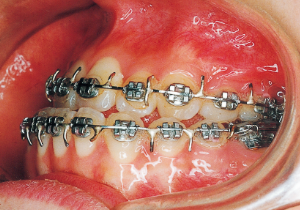

2 After Phase 2 Treatment 5-9-’92

13 5-21-’90 At Phase 2 Treatment

14 6-21-’90 Beginning of second phase

15 3-23-’91 Before surgery

16 5-9-’92 After Phase 2 Treatment

Second Phase Treatment:

Pre-surgical orthodontic period: 9 months

Hospitalization period: 2 weeks

Intermaxillary fixation period: Approximately 1 month (orthodontic treatment was not possible during this period).

Post-surgical orthodontic period: 10 months

Retention period: 2 years 5 months